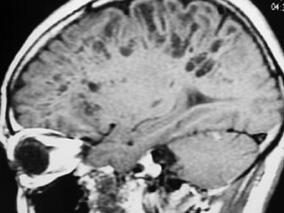

1小时条评论男,43岁,右利手。 主诉:进行性四肢无力2年余。 病史:患者于2年前无明显诱因下出现右侧肢体无力,右臂上举费力,穿衣服可,晒衣服费力,上楼时觉右下肢发软,但仍能上五楼,偶觉持筷时手指僵硬感,无肢体疼痛,偶有肌肉跳动感。于外院诊断为颈椎病,经治疗无效...